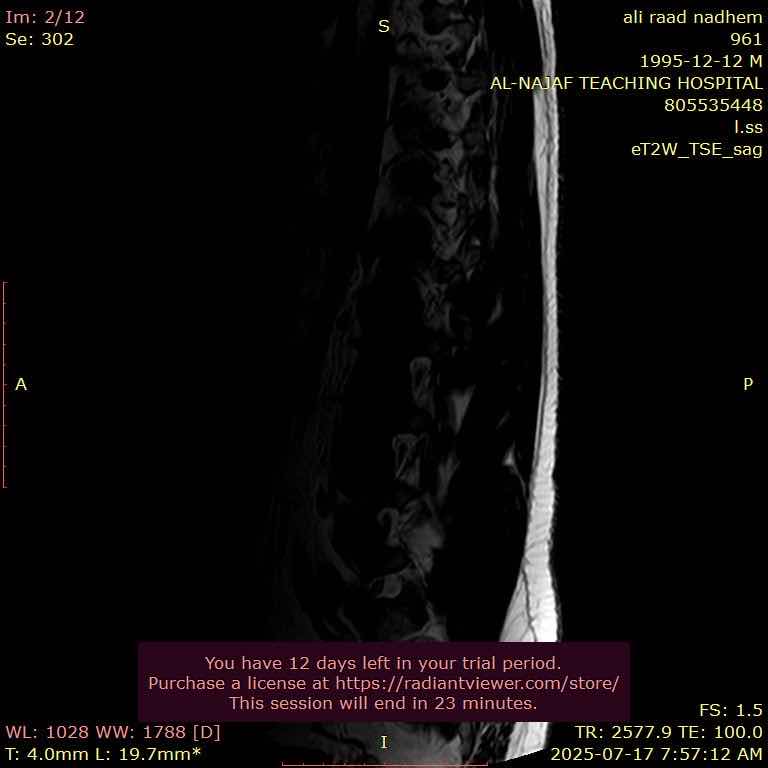

اني عندي انزلاق غضروفي ب3 فقرات اسفل الظهر واريد اراجع دكتور ايهما افضل الي دكتور جملة عصبية او دكتور مفاصل او دكتور كسور

828B877A-5512-472F-90CC-0E3C8F8BAE48 F02F47FA-A8E2-47D8-87B5-78739789E496